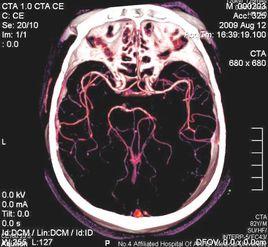

CT血管成像(CTA)指靜脈注射含碘造影劑後,經計算機對圖像進行處理後,可以三維顯示顱內血管系統,可以取代部分DSA檢查。CTA可清楚顯示大腦動脈環(Willis環),以及大腦前、中、後動脈及其主要分支,對閉塞性血管病變可提供重要的診斷依據。可以將缺血性腦血管病的診斷提早到發病後2小時。

CT血管造影隨著介入放射學的發展,血管造影已經成為臨床的一種重要的診斷方法,尤 其在介入治療中起著不可替代的作用。血管造影在頭頸部及中樞神經系統疾病、心臟大血管疾病、及腫瘤和外周血管疾病的診斷和治療中都發揮著重要作用。